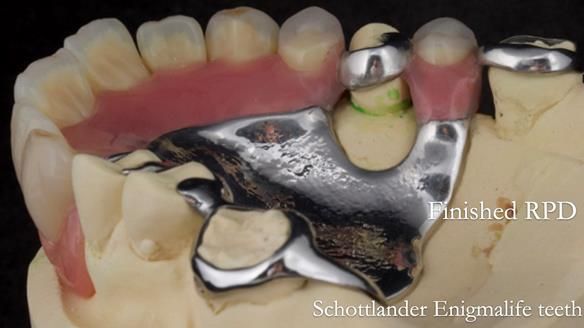

- New metal based upper and lower RPDs of Scandinavian design for improved, periodontal health, function and appearance.

The clinical situation and treatment process is shown in detail below with photographs. I provided the clinical work. Rowan Garstang provided the technical work.